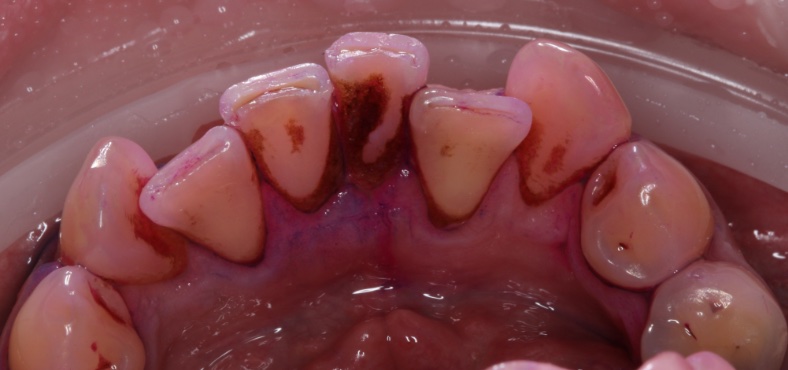

Наши работы

• Профессиональная гигиена